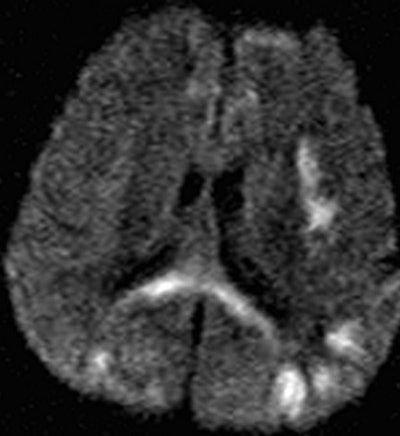

Above is a T2-weighted MR image of bilateral patchy hyperintense lesions in the cerebral cortex, including the insula (arrow). There is also involvement of the splenium of the corpus callosum (arrowhead). On the corresponding diffusion-weighted MR image below, the hyperintense lesions are more prominent than above. |

In seven patients, there was cortical involvement that the authors described as "patchy noncontiguous" in four cases and "confluent" in three patients, with sparing of the subcortical white matter and cerebellum. Three patients displayed abnormalities of the splenium of the corpus callosum in addition to the cortex.

"These findings are consistent with those of previous studies that described selective vulnerability of the brain to hypoglycemic damage and characteristic lesion distribution," the authors wrote.

In patients who have taken sexual enhancement products containing glibenclamide, the ability of diffusion-weighted MRI to discover cortical and hippocampal abnormalities, with additional involvement of the corpus callosum and internal capsule in some cases, can be most beneficial, the authors concluded.